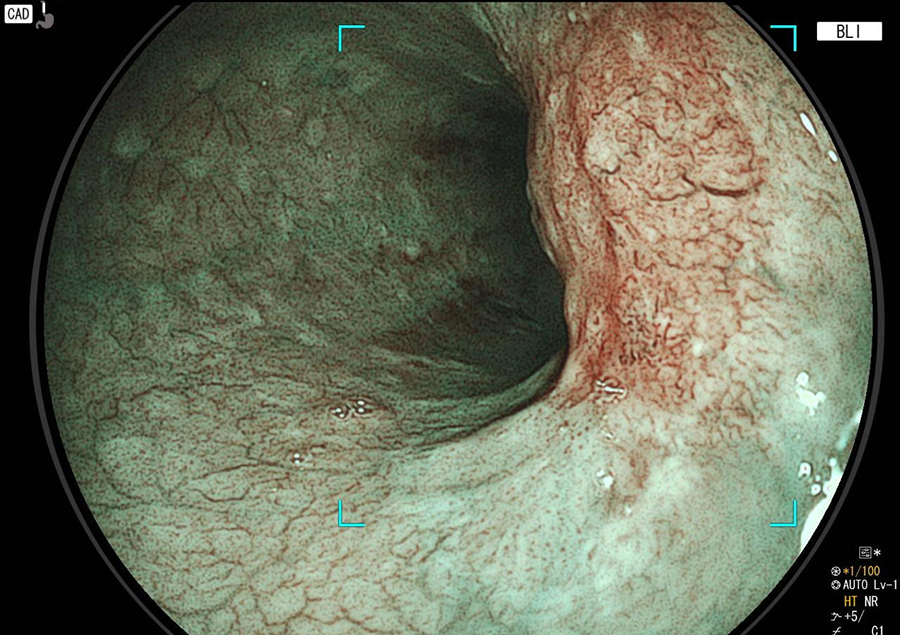

胃カメラ検査では、口又は鼻から内視鏡を挿入し、食道・胃・十二指腸の一部を観察します。直接胃や食道の粘膜を観察することができるので、色調や微妙な凹凸の変化が分かり、潰瘍・炎症・ポリープ・腫瘍などの診断が可能です。

胃カメラでわかる病気/病変

- 胃炎、ピロリ感染胃炎